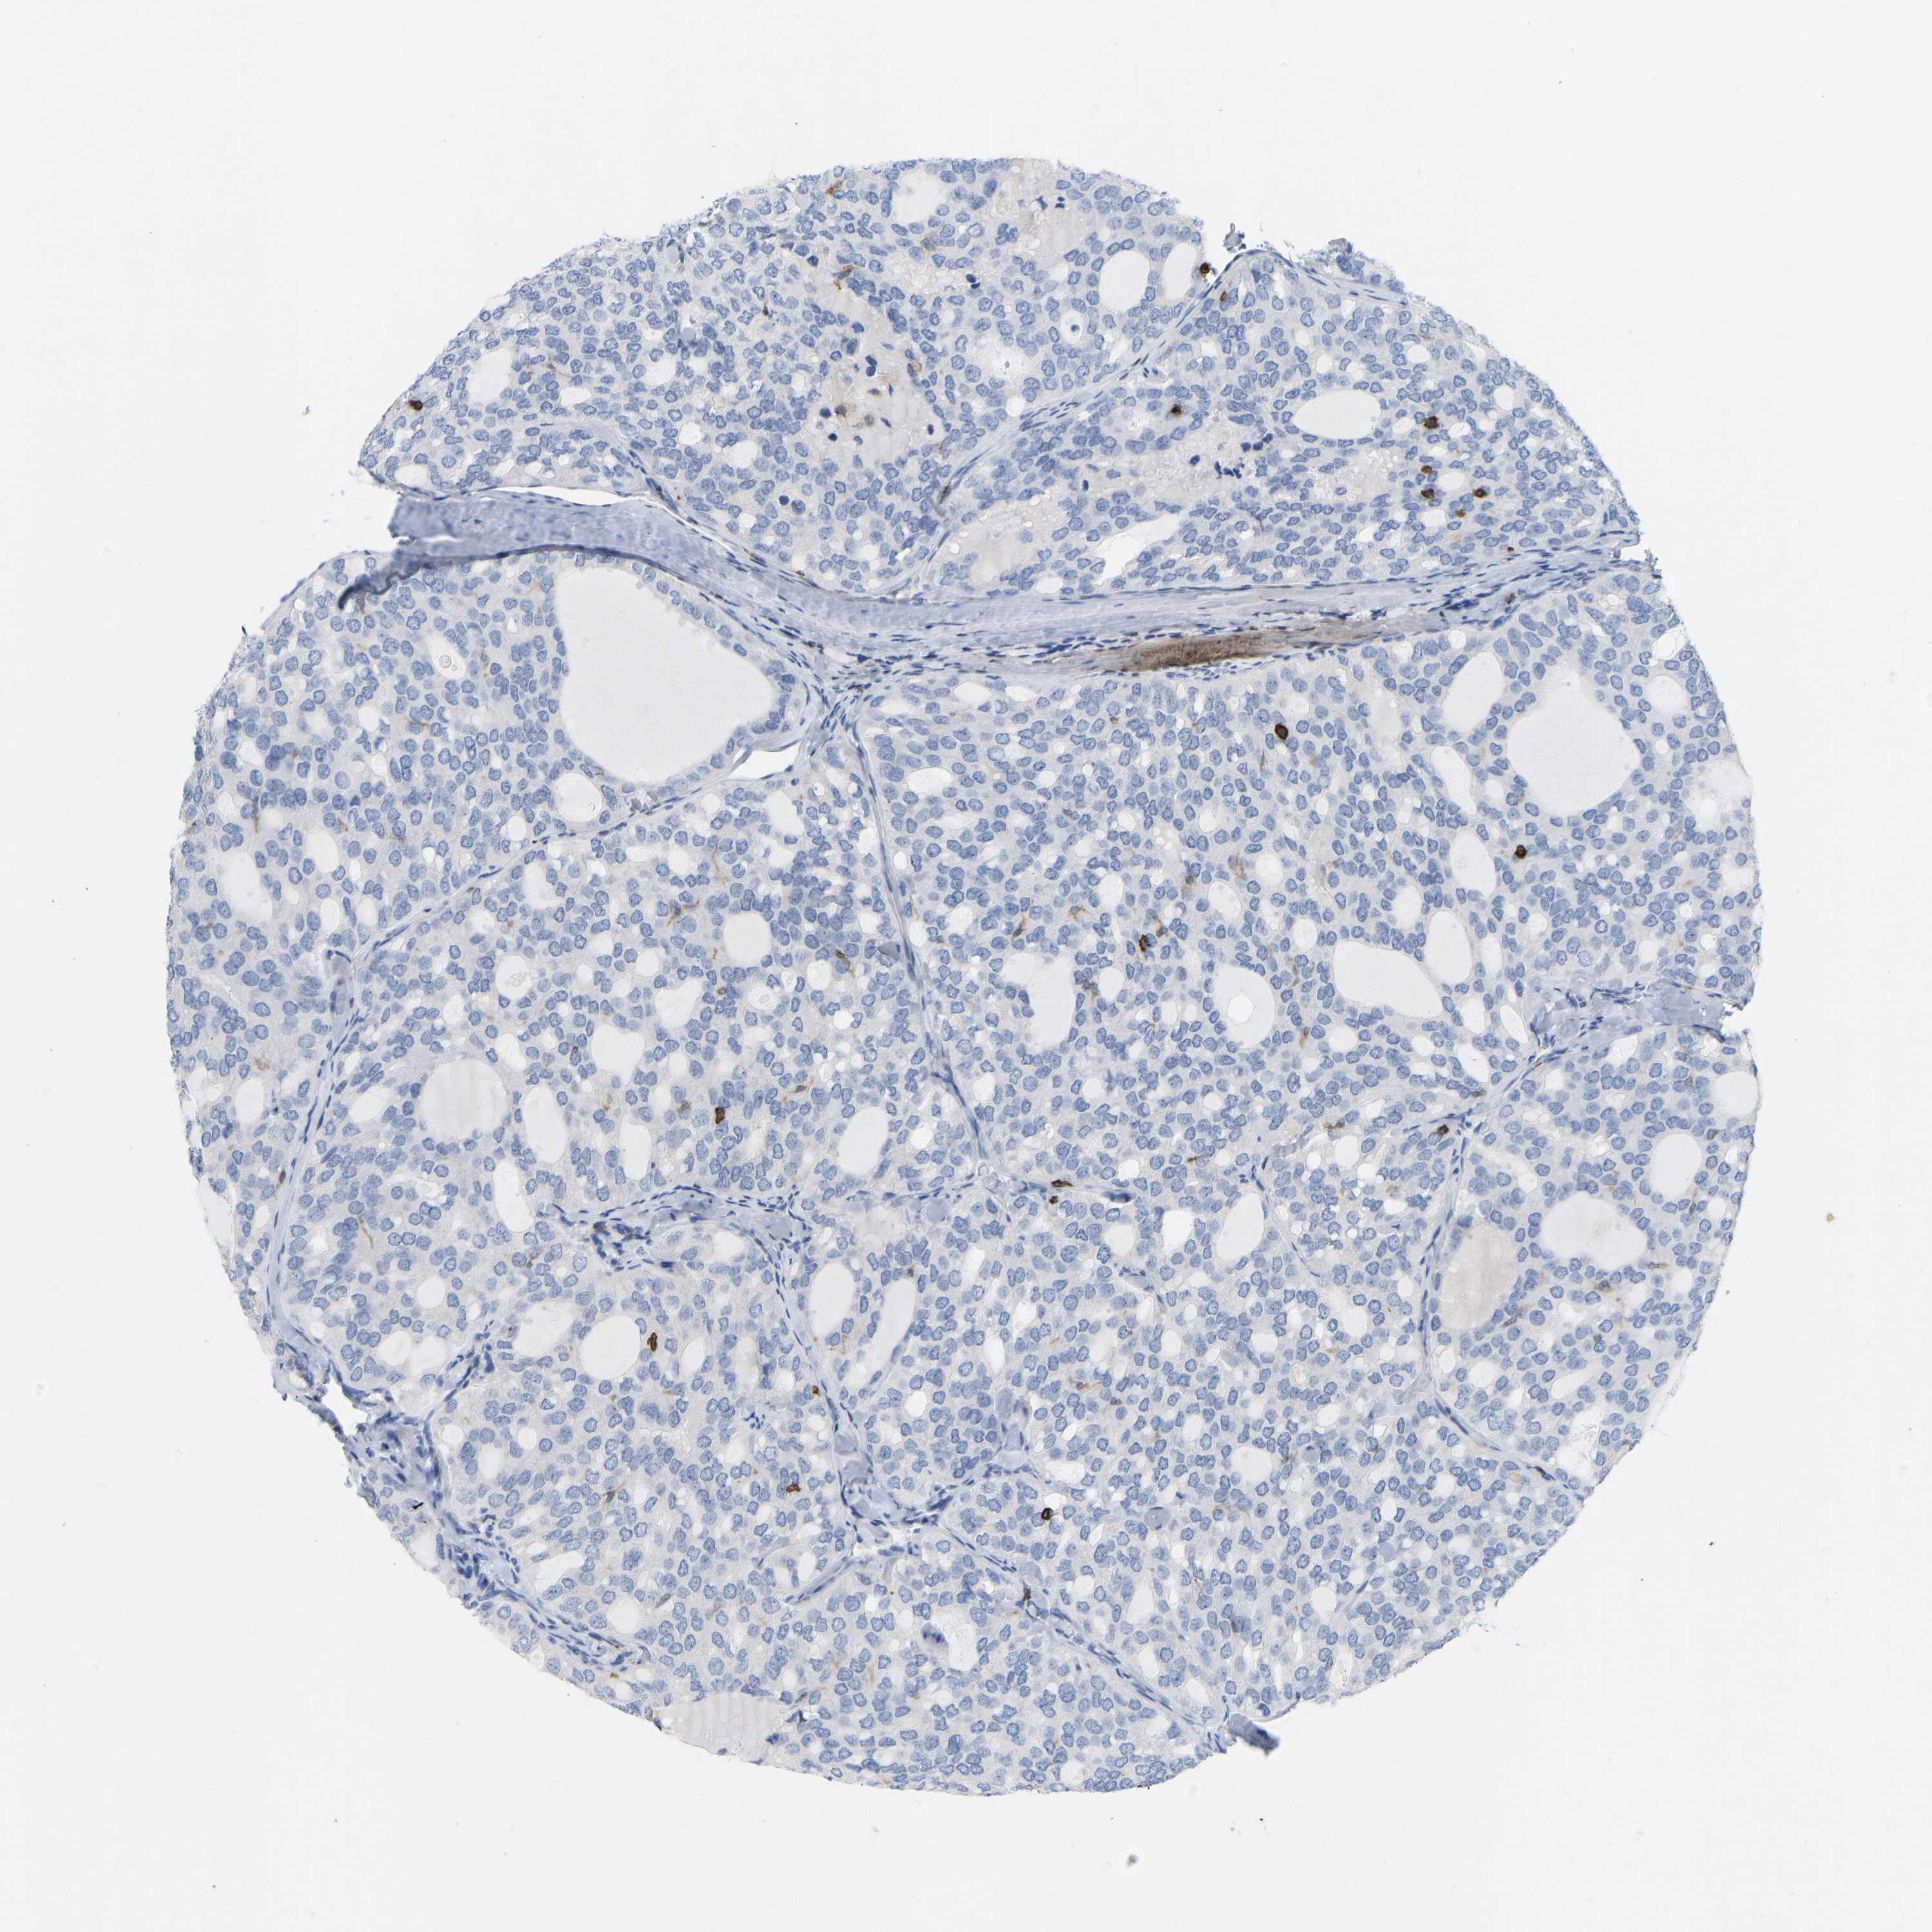

THYROID CANCER - Protein expressioni

A mouse-over function shows sample information and annotation data. Click on an image to view it in a full screen mode. Samples can be filtered based on level of antibody staining by selecting one or several of the following categories: high, medium, low and not detected. The assay and annotation is described here.

Note that samples used for immunohistochemistry by the Human Protein Atlas do not correspond to samples in the TCGA dataset.

Antibody stainingi

Antibody staining in the annotated cell types in the current human tissue is reported as not detected, low, medium, or high, based on conventional immunohistochemistry profiling in selected tissues. This score is based on the combination of the staining intensity and fraction of stained cells.

Each image is clickable and will lead to virtual microscopy that enables deeper exploration of all samples and also displays staining intensity scores, fraction scores and subcellular localization as well as patient and tissue information for each sample.

Antibody HPA018849

Antibody HPA019536

Antibody CAB033987

Staining

High

Medium

Low

Not detected

Intensity

Strong

Moderate

Weak

Negative

Quantity

>75%

75%-25%

<25%

None

Location

Nuclear

Cytoplasmic/membranous

Cytoplasmic/membranous,nuclear

Papillary adenocarcinoma, NOS

Follicular adenoma carcinoma, NOS